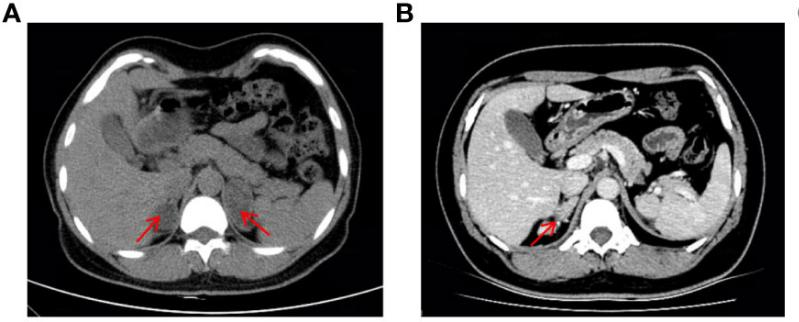

¸Ã»¼ÕßÊÇÒ»Ãû37ËêµÄÅ®ÐÔ£¨ºËÐÍΪ46£¬£¬£¬£¬£¬£¬£¬XX£©£¬£¬£¬£¬£¬£¬£¬Í¯Äêʱ±£´æÉú³¤¼ÓËÙ£¬£¬£¬£¬£¬£¬£¬ÇÒ»éºóһֱδÓÐÉí¡£¡£¡£¡£¡£¡£¡£2019ÄêÒòÒÉÕïË«²àÉöÉÏÏÙÖ×ÁöÈëÔº£¨Í¼1A£©£¬£¬£¬£¬£¬£¬£¬Ç°ºó¾ÙÐÐÁËÁ½´ÎÉöÉÏÏÙÇгýÊõ¡£¡£¡£¡£¡£¡£¡£2022Ä꣬£¬£¬£¬£¬£¬£¬»¼ÕßÓÉÓÚÔ¾²»¹æÔò±»ÊÕÈëÄÚÉøÍ¸¿Æ£¬£¬£¬£¬£¬£¬£¬CTÏÔʾÓÒÉöÉÏÏÙÆ¤ÖÊÔöÉú¸´·¢£¨Í¼1B£©£¬£¬£¬£¬£¬£¬£¬Ìå¸ñ¼ì²éÏÔʾ¸Ã»¼Õ߯¤·ôÉ«ËØÀä¾²£¬£¬£¬£¬£¬£¬£¬Ã沿ÓÐðî´¯ºÍ÷×룬£¬£¬£¬£¬£¬£¬·ºÆðÄÐÐÔ»¯ÌåÕ÷£¬£¬£¬£¬£¬£¬£¬Éú»¯¼ì²éÌáÐѵͼØÐÔ¸ßѪѹ£¬£¬£¬£¬£¬£¬£¬¸ßÐÛѪ֢¡£¡£¡£¡£¡£¡£¡£¾ùÌáÐÑ11¦Â-OHDÕï¶Ï¡£¡£¡£¡£¡£¡£¡£

ͼ1 »¼Õ߸¹²¿CTÓ°Ïñ